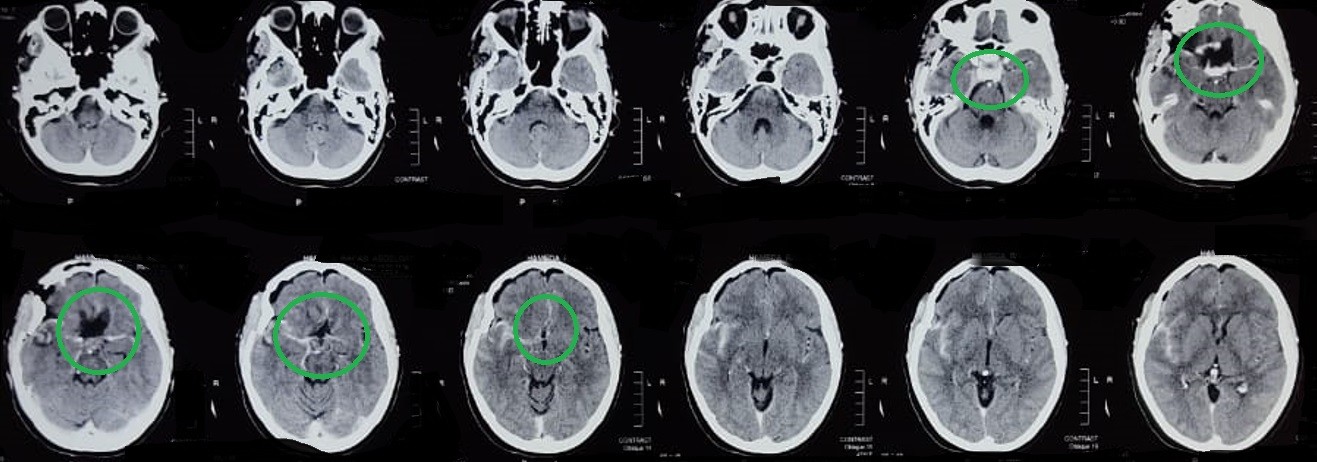

sphenoidal meningioma